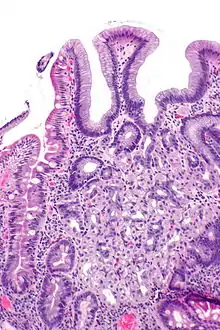

In medicine, heterotopia is the presence of a particular tissue type at a non-physiological site, but usually co-existing with original tissue in its correct anatomical location. In other words, it implies ectopic tissue, in addition to retention of the original tissue type. In neuropathology, for example, gray matter heterotopia is the presence of gray matter within the cerebral white matter or ventricles. Heterotopia within the brain is often divided into three groups: subependymal heterotopia, focal cortical heterotopia and band heterotopia. Another example is a Meckel's diverticulum, which may contain heterotopic gastric or pancreatic tissue.